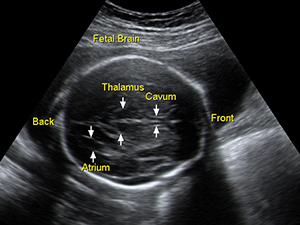

中孕期的胎兒腦部